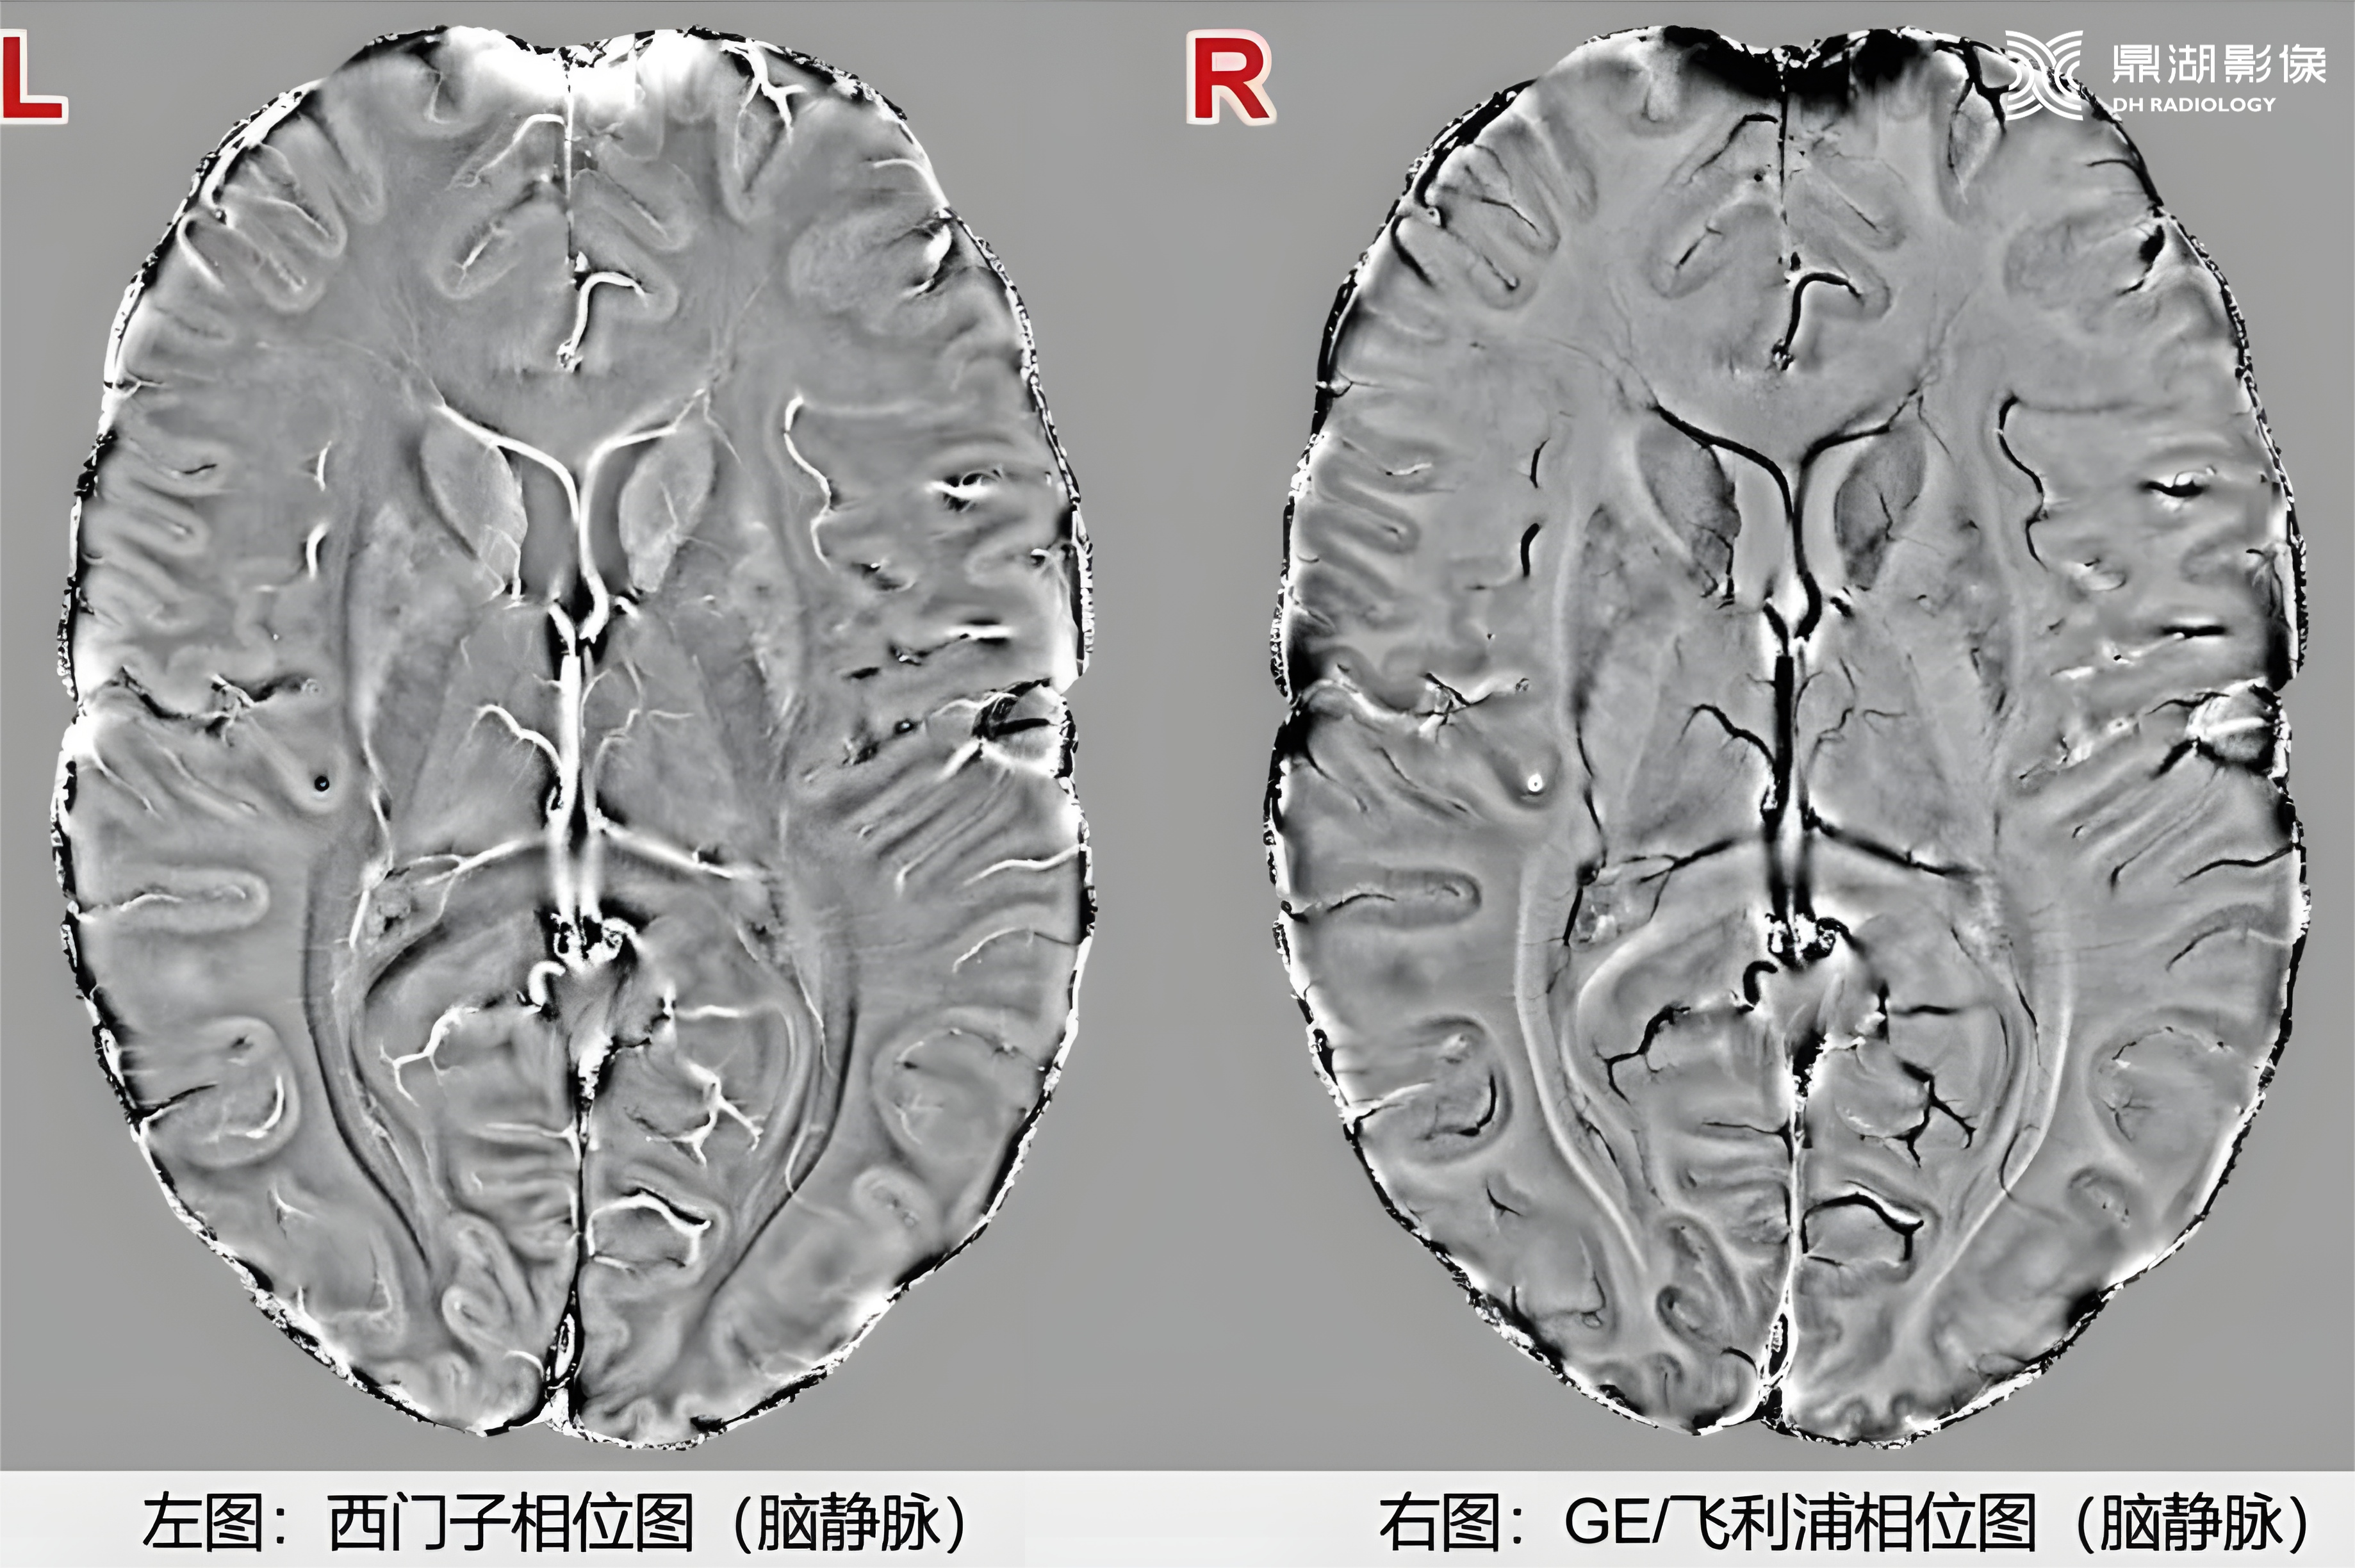

在SWI图像判断时,西门子设备上钙化在相位图呈低信号,而GE、飞利浦上呈高信号,这是因为不同厂商采用的相位坐标系统不同

左手定则:拇指朝上时,其余四指为顺时针方向,那就代表顺磁性的(比如铁沉积)为高信号(拇指朝上代表高信号,朝下代表低信号)。西门子磁共振采用的是左手定则。

右手定则:拇指朝上时,其余四指为逆时针方向,那就代表逆磁性的(比如铁钙化)为高信号(拇指朝上代表高信号,朝下代表低信号)。飞利浦和GE的磁共振设备采用的是右手定则。

不同厂商磁共振设备的SWI相位图信号差异,源于相位坐标系的左右手系统区别:

01

右手坐标系(飞利浦、GE)

坐标特性:顺磁性物质产生负相移,相移越大相位图越亮(灰度越高)。

信号表现:

出血(顺磁性):相位图呈低信号,幅度图及 MIP 图呈低信号。

钙化(抗磁性):相位图呈高信号,幅度图及 MIP 图呈低信号。

左手坐标系(西门子、佳能)

坐标特性:顺磁性物质产生正相移,相移越大相位图越亮(灰度越高)。

出血(顺磁性):相位图呈高信号,幅度图及 MIP 图呈低信号。

钙化(抗磁性):相位图呈低信号,幅度图及 MIP 图呈低信号。